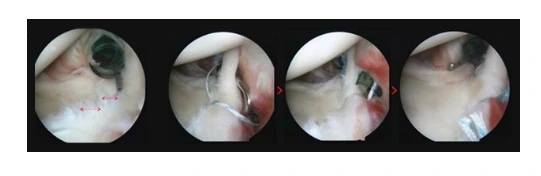

관절내시경 봉합술

어깨관절와순파열이 중기 이상으로 진행되었다면 수술을 선택해야 하는데요. 파열이 생기면 어깨 불안정성이 생겨 회전근개 힘줄에도 문제를 일으킬 수 있으니 수술로 찢어진 부위를 봉합해야 합니다.

특히, 젊고 신체 활동을 많이 한다면 일단 한 번 파열된 부위가 반복되는 움직임으로 점점 더 크게 발전될 수 있어 파열된 관절와순을 봉합하는 수술이 바람직하지요.

어깨수술.PNG

전영식 원장님 “에이스병원에서는 환자들의 병변 위치와 정도에 맞춰 개별화된 수술을 진행합니다. 수술에서는 무나사봉합사와 정밀한 관절경내시경으로 진행하고 있어서 수술 후 통증이 적고 입원기간도 짧지요”라고 관절내시경 봉합술에 대해 알려주시며 “어깨관절와순파열 수술은 수술을 하고 나서 재활이 중요하다”라고 당부하십니다.